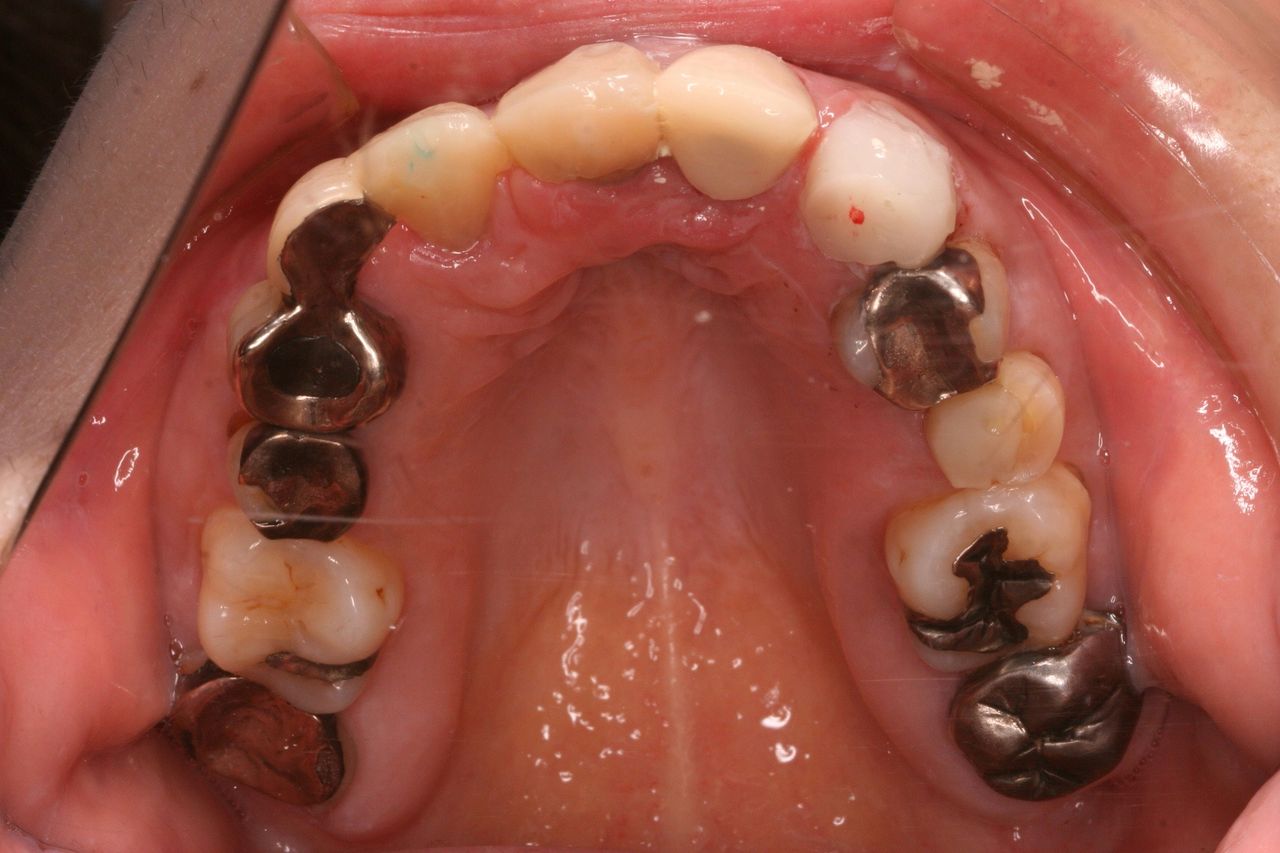

おおよそ1年間の治療期間で歯の根っこと矯正治療が終了しました。

この後、下の前歯1本が暗いのでホワイトニングをし、上下の歯のかぶせ物をやりなおす治療へと移行していきます。

上からみてもかなり左右対称な関係になります。

この方の治療終了は年内目標ですので、年内には完了した画像を動画で提供できたらいいですね!